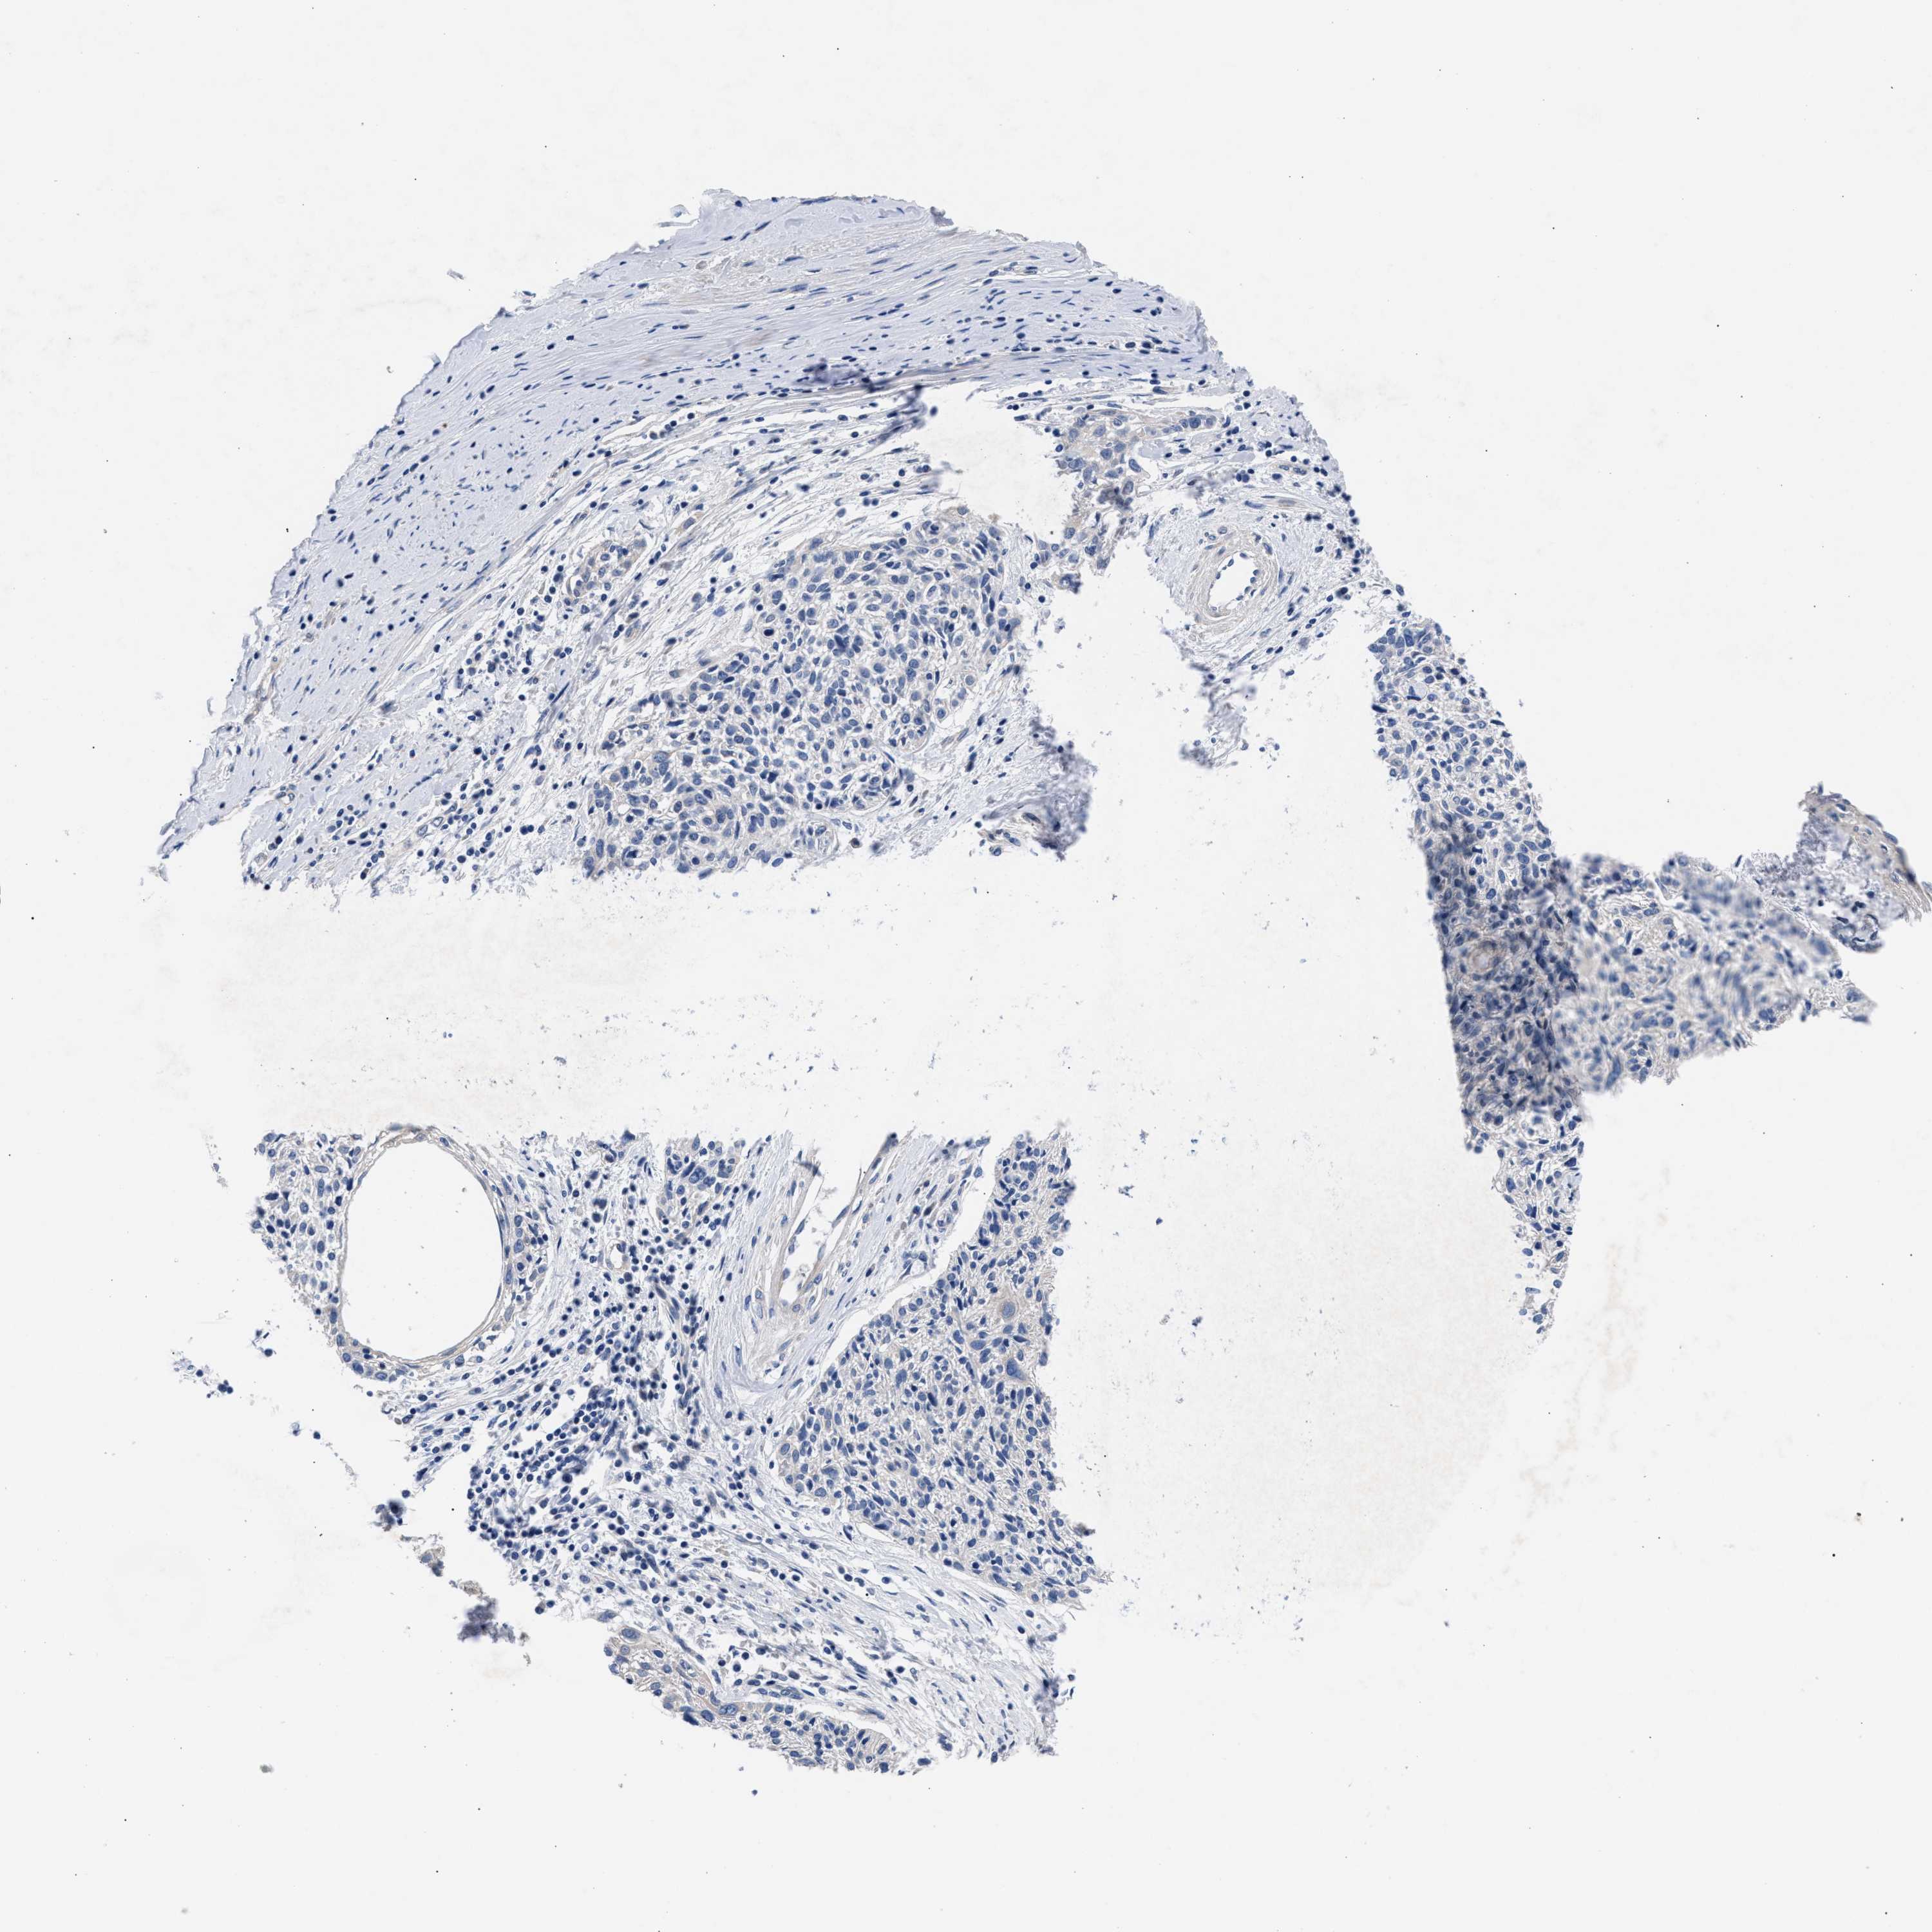

CERVICAL CANCER - Protein expressioni

A mouse-over function shows sample information and annotation data. Click on an image to view it in a full screen mode. Samples can be filtered based on level of antibody staining by selecting one or several of the following categories: high, medium, low and not detected. The assay and annotation is described here.

Note that samples used for immunohistochemistry by the Human Protein Atlas do not correspond to samples in the TCGA dataset.

Antibody stainingi

Antibody staining in the annotated cell types in the current human tissue is reported as not detected, low, medium, or high, based on conventional immunohistochemistry profiling in selected tissues. This score is based on the combination of the staining intensity and fraction of stained cells.

Each image is clickable and will lead to virtual microscopy that enables deeper exploration of all samples and also displays staining intensity scores, fraction scores and subcellular localization as well as patient and tissue information for each sample.

Antibody HPA020974

Staining

High

Medium

Low

Not detected

Intensity

Strong

Moderate

Weak

Negative

Quantity

>75%

75%-25%

<25%

None

Location

Nuclear

Cytoplasmic/membranous

Cytoplasmic/membranous,nuclear

Squamous cell carcinoma, NOS

Adenocarcinoma, NOS